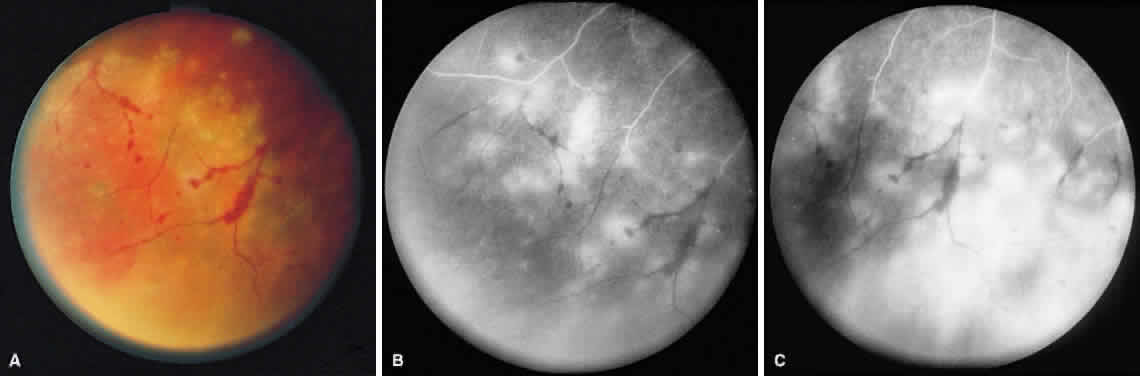

ARN is characterized by a retinal vasculitis affecting both the arteries and veins in the fundus, which is manifested by sheathing of the larger vessels (Fig. 2).7–10,16 Initially, patchy areas of peripheral retinal whitening (“thumbprint lesions”) representing full-thickness retinal necrosis are present or develop shortly after the vasculitis (Fig. 3). During a course that may span days or weeks, these patches coalesce into geographic areas (Fig. 4A). The entire peripheral retina (360 degrees) may be involved, or, more commonly, there are several noncontiguous patches of necrosis, each covering from a half to three clock hours (Figs. 5 and 6). The posterior segment lesions may not be detected without examination of the peripheral retina.

Fig. 4. A. With progression of ARN, the areas of retinal whitening begin to coalesce. Mild perivascular retinal hemorrhages are noted. B. Fluorescein angiography in the venous phase reveals retinal vascular nonperfusion in areas of active retinitis. C. In the late-phase angiogram, fluorescein hyperfluorescence is seen in areas of retinitis and around the retinal vasculature.

As the infection progresses, the leading edge of confluent retinal whitening advances toward the posterior pole (Fig. 7A). The retinitis may not progress posteriorly to the vascular arcades, sparing the macula and central vision. It is hypothesized that the retinal necrosis in ARN results from the combined effect of intracellular viral replication with subsequent cell death and vascular occlusion secondary to acute vasculitis. In some patients, the retinal vasculitic component may be much more prominent than the retinal necrosis.7 Optic disc swelling, either hyperemic or pallid, is a common feature of the ARN syndrome.1 Perivascular hemorrhages may be present (Fig. 8); however, widespread areas of retinal hemorrhage are atypical. Retinal vascular occlusion, often involving the arteries, can occur at any point during the clinical course. Without treatment, the inflammatory component of ARN typically burns out in 6 to 12 weeks, leaving behind a thin atrophic retina with associated pigmentary changes.10

Fig. 7. A. Active ARN with diffuse retinal necrosis progressing into the macula and areas of retinal hemorrhage. The hazy view is secondary to vitreous inflammation. B. Fluorescein angiogram in the venous phase of active ARN syndrome in this eye reveals peripheral vascular nonperfusion, as well as optic nerve and perivascular hyperfluorescence.